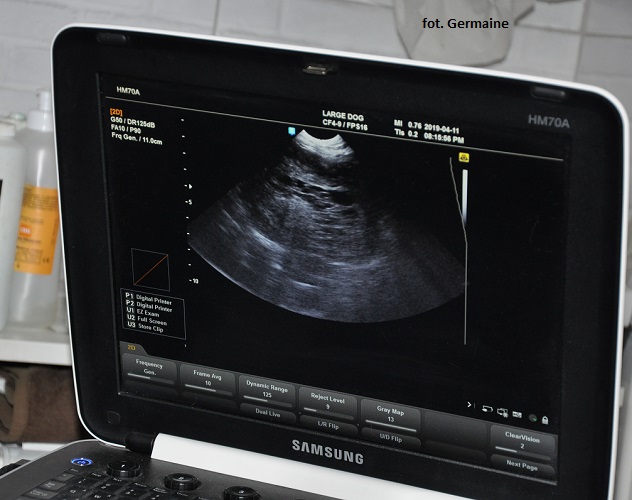

Goldi był dzisiaj na wizycie u kardiologa. Wykonano mu badanie echokardiograficzne serca, które wykazało widoczną zmianę rozrostową przylegającą do łuku aorty i lewego przedsionka.

Goldi w czwartek zwymiotował, był osowiały, pojechaliśmy od razu do lecznicy. Pani Doktor wykonała USG jamy brzusznej, które niestety wykazało obecność guza zlokalizowanej w okolicy śledziony, około 7-8 cm z licznymi kawernami.

Opis badania:

Brak wolnego płynu na terenie jamy brzusznej. Została pobrana krew na morfologię.

Goldi był dzisiaj na wizycie u kardiologa. Wykonano mu badanie echokardiograficzne serca, które wykazało widoczną zmianę rozrostową przylegającą do łuku aorty i lewego przedsionka.

Goldi w czwartek zwymiotował, był osowiały, pojechaliśmy od razu do lecznicy. Pani Doktor wykonała USG jamy brzusznej, które niestety wykazało obecność guza zlokalizowanej w okolicy śledziony, około 7-8 cm z licznymi kawernami.

Opis badania:

Brak wolnego płynu na terenie jamy brzusznej. Została pobrana krew na morfologię.